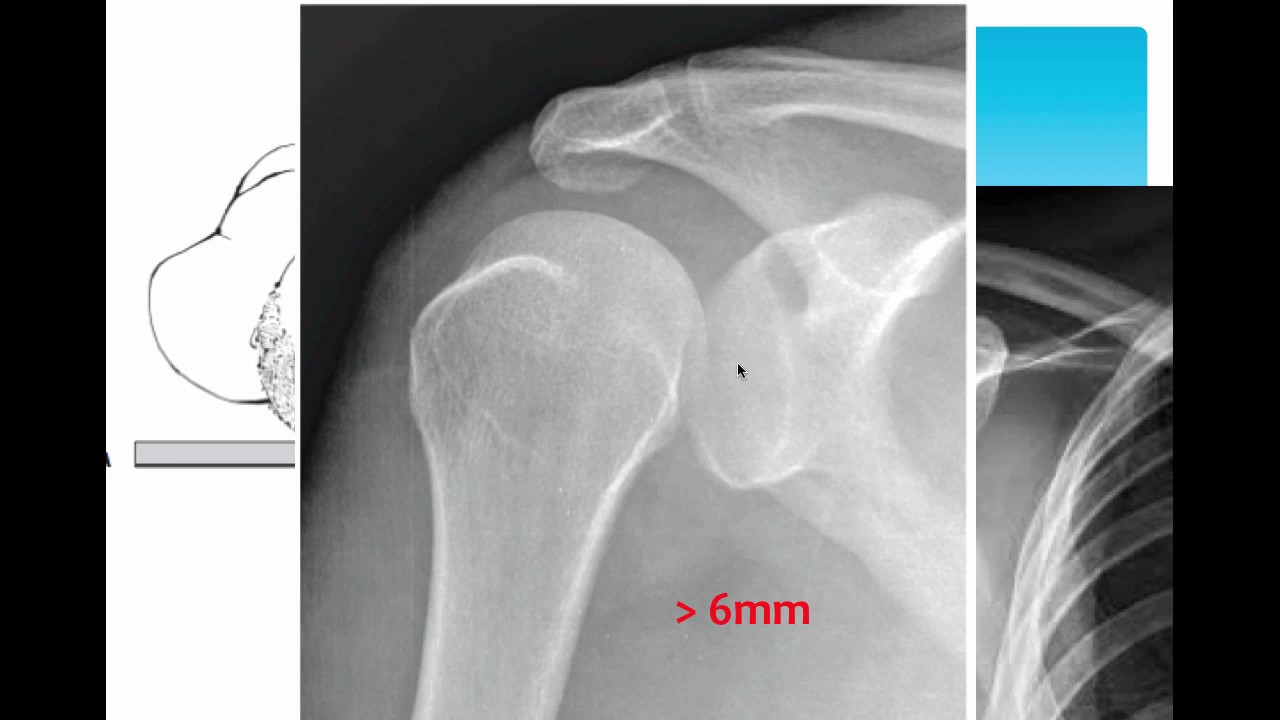

Bác sĩ sẽ kiểm tra các khu vực bị ảnh hưởng, sưng hoặc biến dạng. Điều quan trọng là bạn cần cho bác sĩ biết nguyên nhân gây trật khớp vai và đã từng bị trật khớp trước đó hay không. Bác sĩ sẽ xem xét vai và có thể yêu cầu chụp X-quang để xem các khớp và xương bị gãy hoặc tổn hại khác về khớp vai.